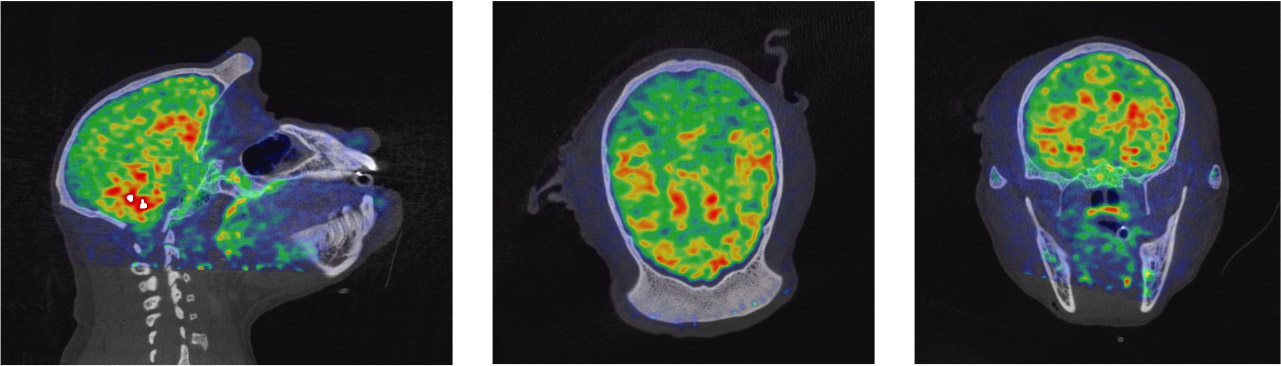

CASE 1: NHP PET/CT FDG brain imaging

• Courtesy of: University of Tours, Preclinical imaging department - PST ASB

Research objective: Investigation of FDG uptake in NHP brainĀ

Animal model: Female Macaca fascicularis, 4.5 kg

Acquisition protocol: PET imaging: 15 min per bed, 2 bed positions, 40 min after injection. CT imaging: 80kV, 52s per bed, 2 bed positions.

Processing and reconstruction protocol: PET: 3D OSEM, 0.84 mm isotropic voxel size. CT: 0.16 mm isotropic voxel size.

Biomarker or contrast agent: 18F-FDG; Injected activity: 85 MBq i.v.